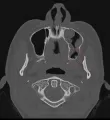

Мне 29 лет. Года полтора назад начал расти зуб мудрости на нижней челюсти. Единственный из 4-х. В то же время я простудился и переболел. После болезни возле челюсти воспалена гланда, увеличены лимфоузлы. Всё со стороны этого зуба. В ухе булькает. На задней стенке горла прямо по центру белая лимфоидная ткань (пузырь), ЛОР при осмотре сказал, что это не по его части.

Зуб сильно не болел когда прорезывался, в соседние зубы не упирается, щёку не задевает. Даже десна возле него не воспалённая. Капюшон над ним ещё небольшой остается, но тоже не воспалённый и легко отходит, чтобы почистить под ним.

Нужно ли зуб удалять при таких процессах в горле или нужно пролечиться сначала у грамотного ЛОРа? Может ли зуб давать такие симптомы или это последствия простуды?